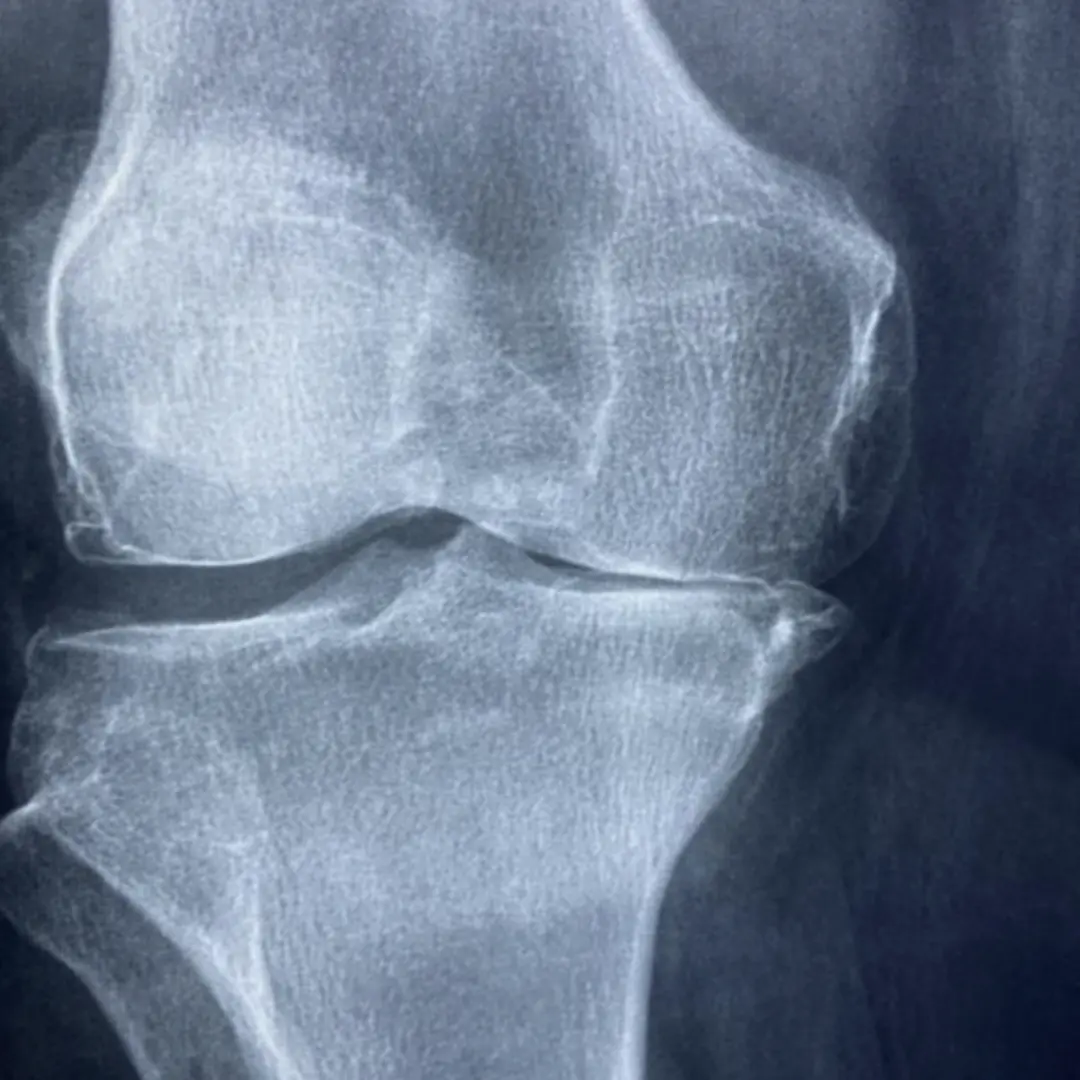

퇴행성관절염은 관절을 보호하고 움직임을 원활하게 하는 연골이 점진적으로 손상되거나 퇴행성 변화를 겪으면서 발생하는 만성 질환이에요. 연골은 뼈와 뼈 사이에서 충격을 흡수하고 마찰을 줄여주는 쿠션 역할을 하는데요. 나이가 들거나 과도한 사용, 외상 등으로 연골이 닳아 없어지면 뼈와 뼈가 직접 부딪히면서 염증과 통증을 유발하게 됩니다.

퇴행성관절염은 주로 무릎, 엉덩이(고관절), 척추, 손가락 끝마디 등 체중을 지탱하거나 많이 사용하는 관절 부위에 잘 발생해요. 관절염의 종류 중 가장 흔한 형태이며, 유전적 요인, 비만, 과도한 운동, 과거 관절 손상 등이 복합적으로 작용하여 발병합니다. 단순히 노화 현상으로만 볼 것이 아니라, 적극적인 관리와 치료가 필요한 질환이에요. 연골이 한번 손상되면 자연적으로 재생되기 어렵기 때문에, 초기에 증상을 인지하고 진행을 늦추는 것이 중요하답니다.